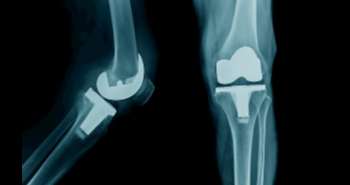

Attempts are proceeding to identify risk factors for rheumatoid arthritis (RA). Where smoking is an essential risk factor for RA, many individuals who never smoked also develop RA, this indicates the involvement of other factors such as diet and obesity as well. Other previous studies say that eating fish is a protective approach for rheumatoid arthritis (RA) risk possibly due to the anti-inflammatory influence of omega-3 fatty acid it contains, although this association has not been established explicitly. Therefore, this prospective cohort study was conducted with large sample size, repeated measures of dietary intake, and extended follow-up to assess the fish intake and RA risk by the age of onset, smoking and serologic status.

A total of 166,013 females from two prospective cohorts, the Nurses' Health Study (NHS) and NHSII were studied for evaluating the fish intake and RA risk association. Food frequency questionnaires were used to estimate the fish intake at baseline and every four years. A medical record review was utilized to assess incident RA during follow-up and serologic status. The estimated hazard ratios (HR) and 95% confidence intervals (CI) for fish intake frequency and RA was determined by applying Pooled Cox Regression. The analysis also investigated the smoking-fish synergy for RA risk.

One thousand eighty incident patients of RA were identified during the 3,863,909 person-years of follow-up. The enhanced intake of fish was not related to all RA or seronegative RA; however, had risen risk for RA diagnosed > 55 years old. The HRs of frequent fish intake (vs infrequent) for RA,  seronegative and seropositive RA among women ≤55 years old noticed to be was 0.73, 0.55, and 0.85, respectively. Smokers with frequent fish intake showed modest raised RA risk, and smokers with infrequent fish intake showed a highly elevated risk for RA onset ≤55 years. No clear protective impact of marine omega-3 fatty acid or fish intake was found on RA risk, overall or by serologic status, however, infrequent consumption of fish with smoking led to the elevated risk of RA.